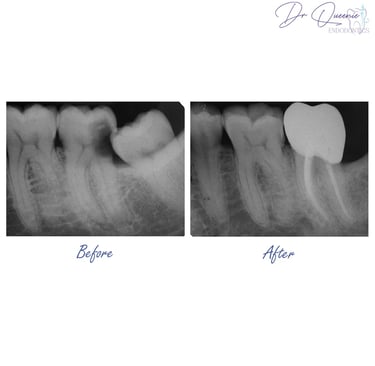

When you visit Lau Dental Clinic and Surgery, our friendly team will welcome you and start with a thorough check-up. An X-ray reveals the problem: the inside of your tooth (called the pulp) is infected. But don’t worry — your tooth can still be saved.

Once cleaned, the space inside your tooth is filled and sealed to prevent future infections. In most cases, we’ll place a crown later to protect your tooth and restore its full strength — so it looks and feels just like before.